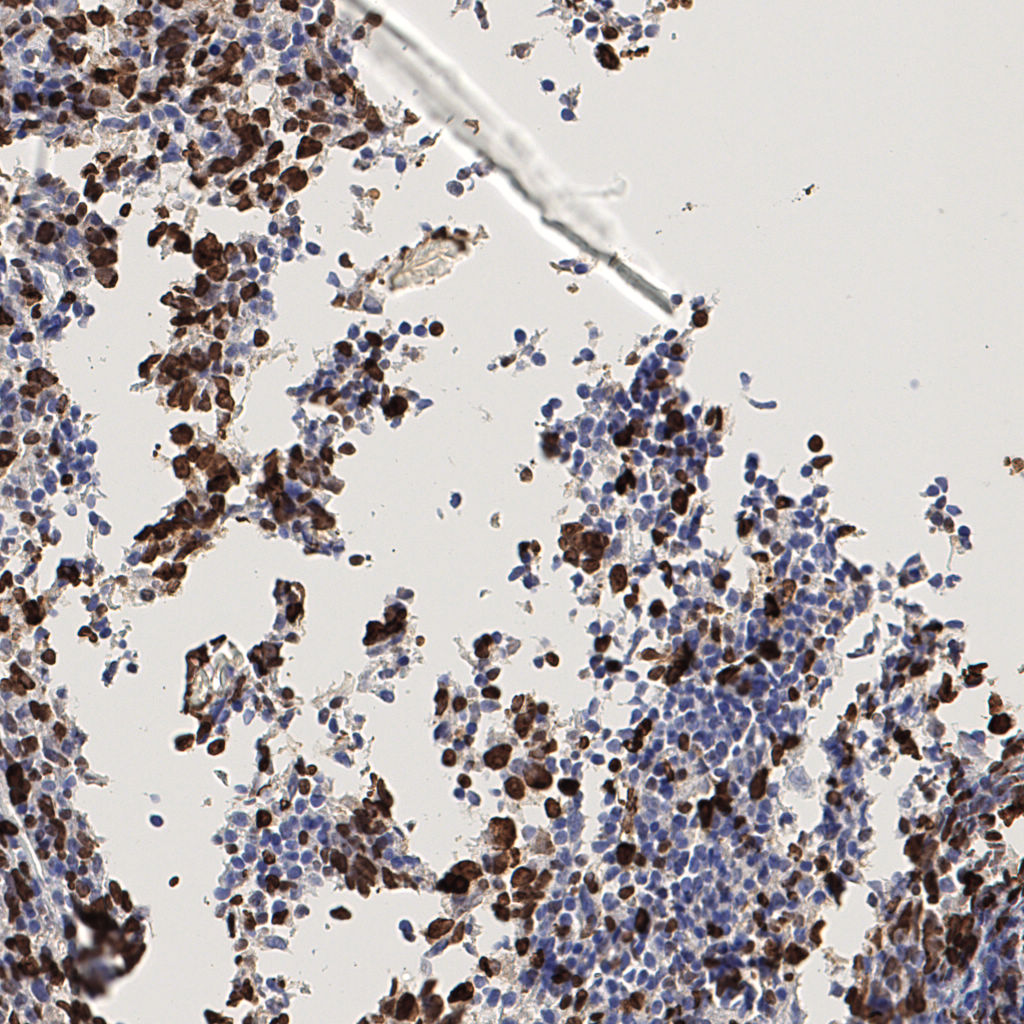

7.85%

Ki67 指数

阴 1104 阳 94

H255858-KI-67.ndpi